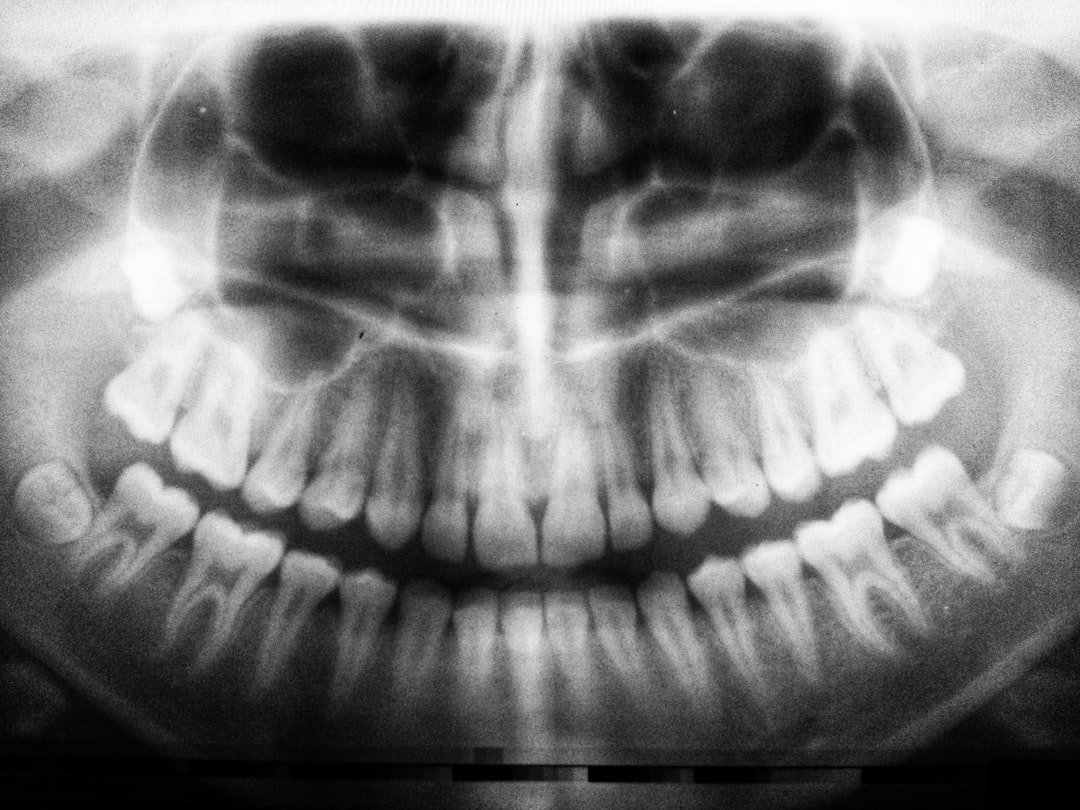

Monitoramento Global da Saúde Bucal

Organizações internacionais, como a OCDE (Organização para a Cooperação e Desenvolvimento Econômico), monitoram há décadas o desempenho de diversas nações em indicadores de saúde.

Esses relatórios nos ajudam a entender as tendências e os fatores que influenciam a qualidade dos sorrisos ao redor do globo.